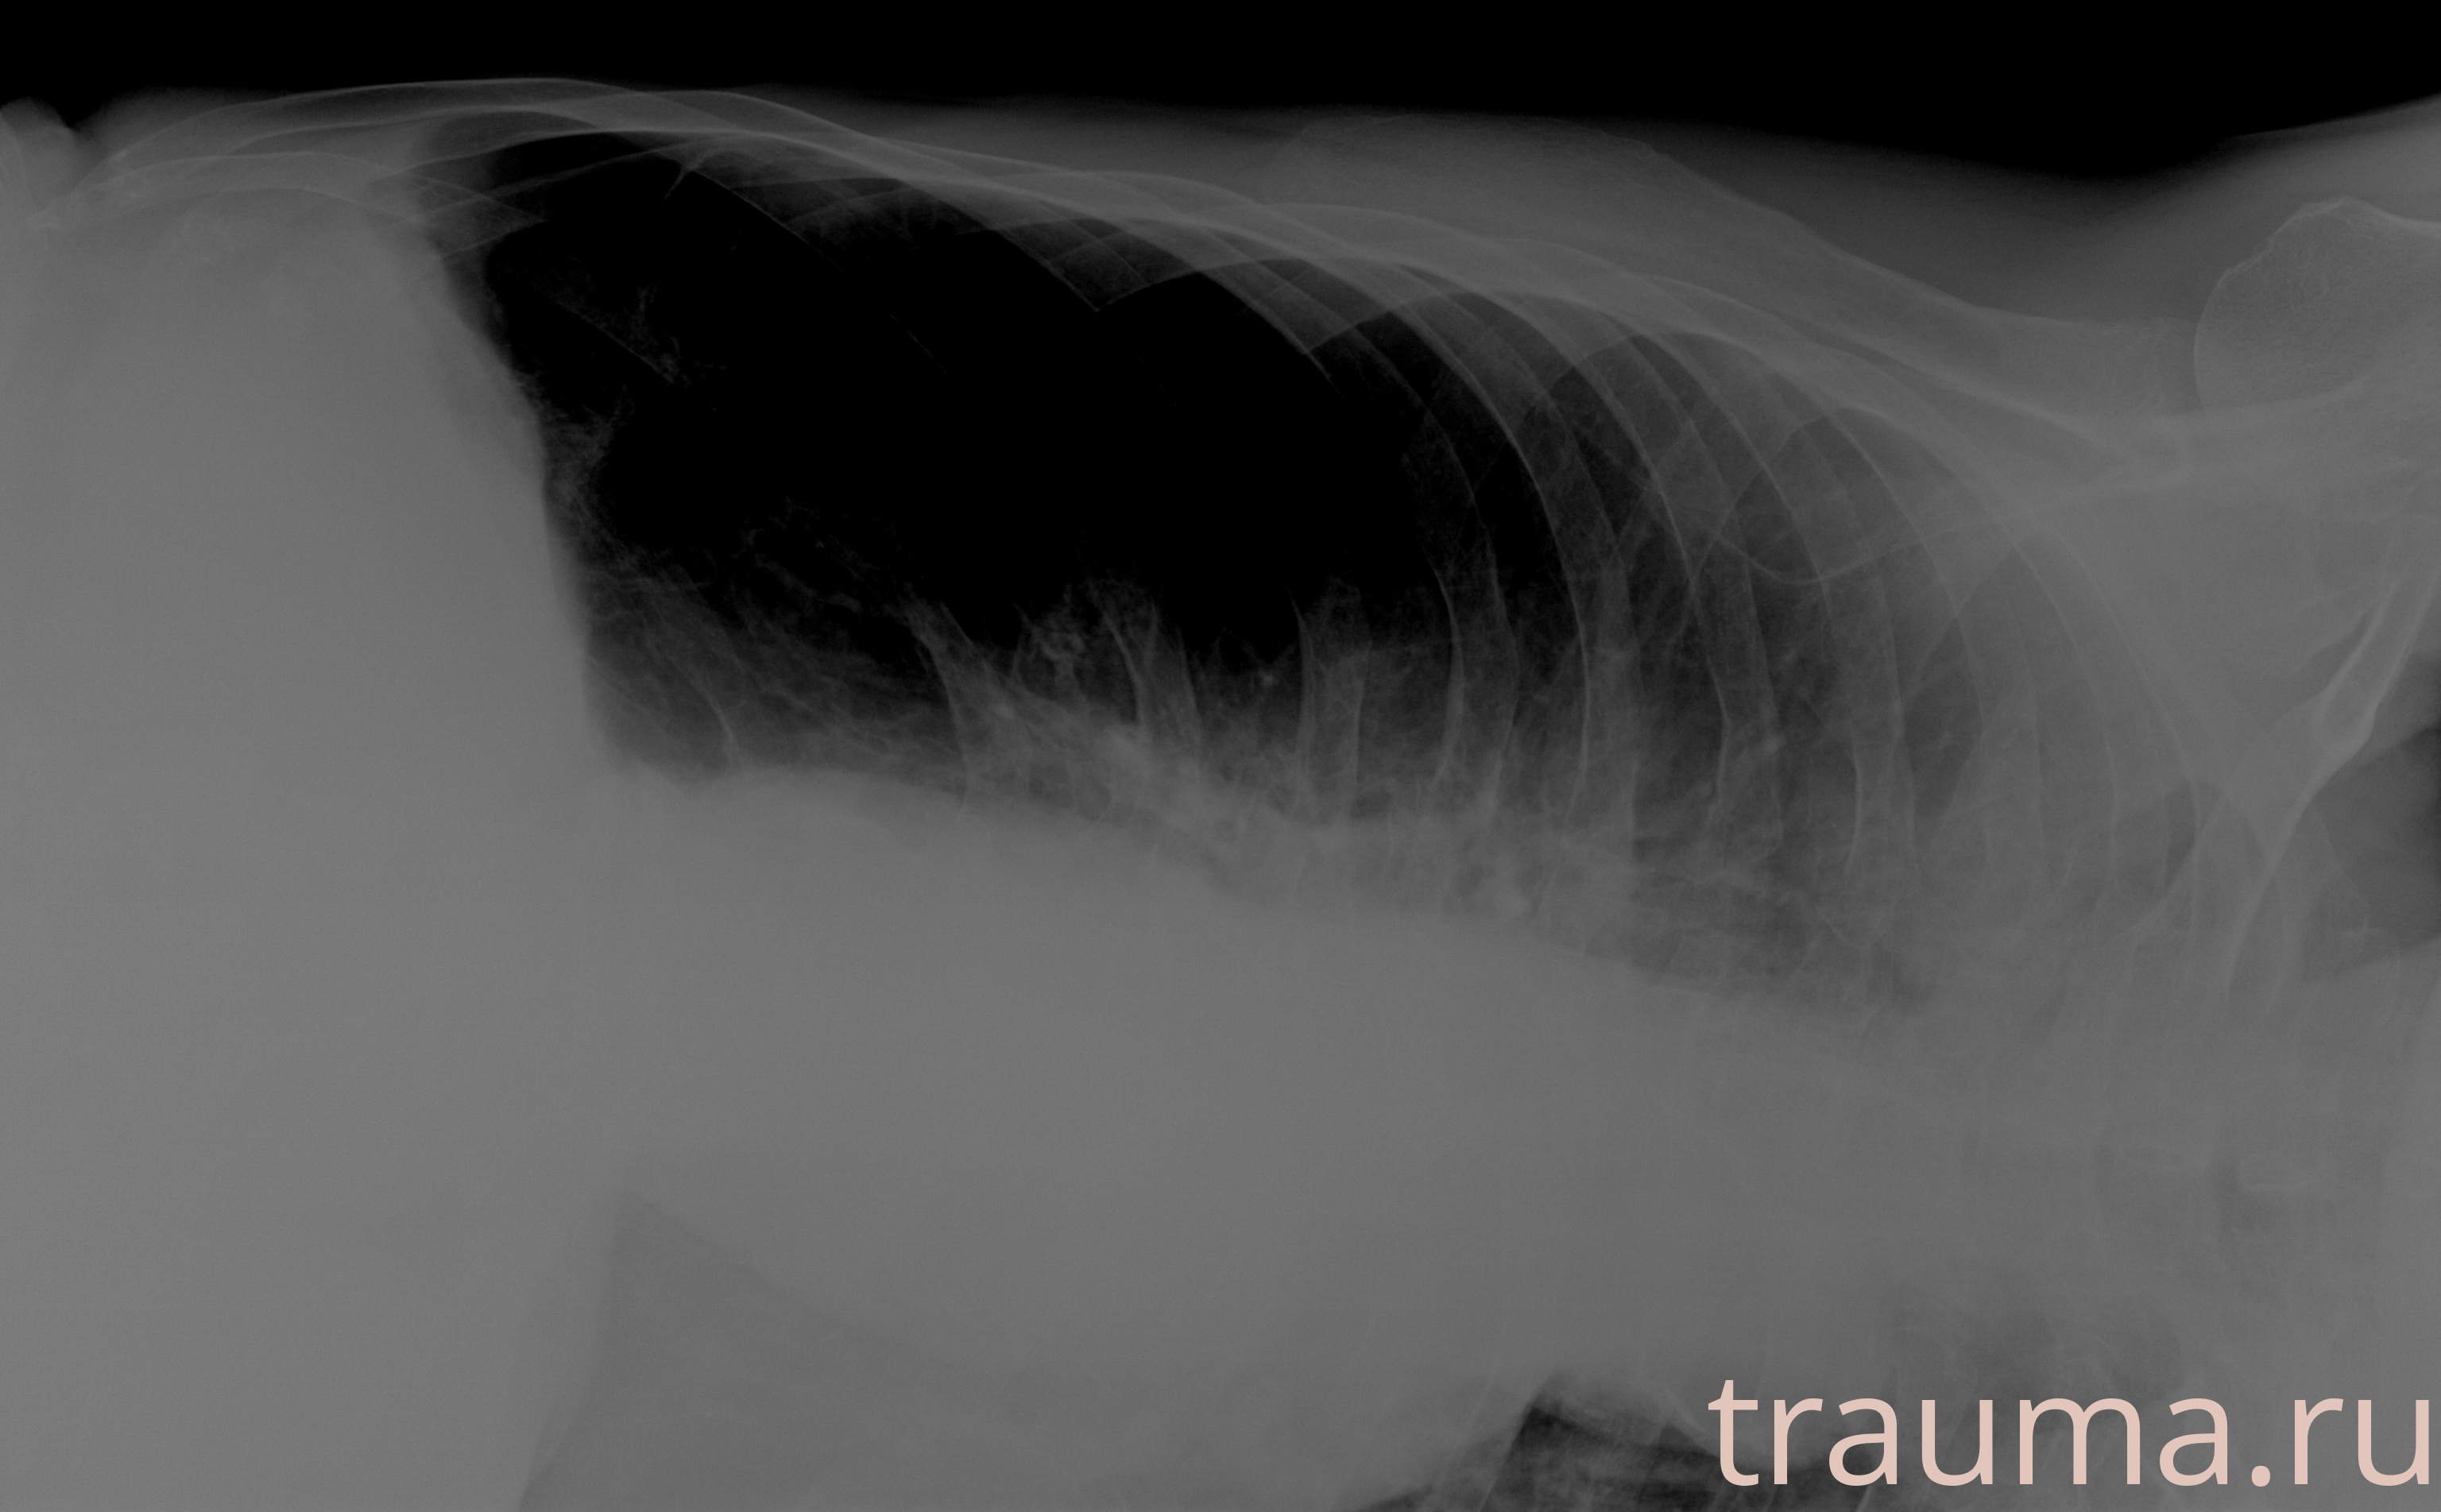

Рентген на дому: по вашему адресу приезжает врач-рентгенолог, травматолог-ортопед с мобильным рентгеновским аппаратом, проводит диагностику травмы или заболевания, делает необходимые рентгенограммы, дает рекомендации по дальнейшему лечению. Получить качественные снимки в домашних условиях возможно благодаря уникальной методике, разработанной МосРентген Центром для института  Склифосовского